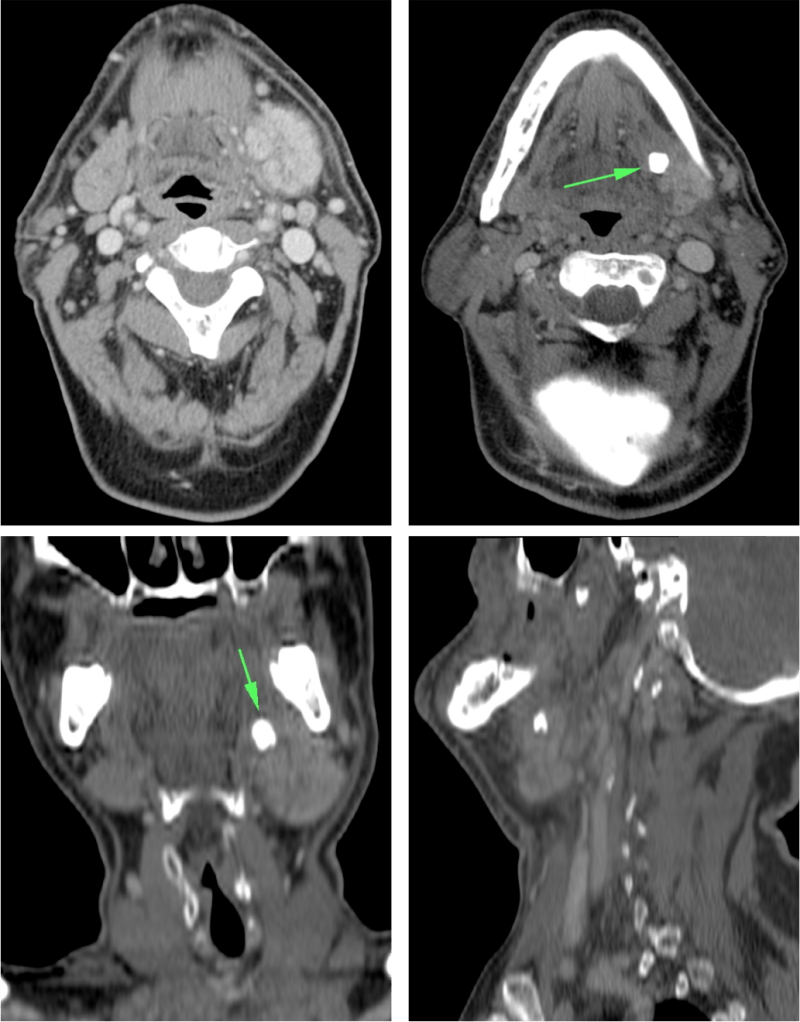

Quistes del segundo arco branquial:

Pueden localizarse en el espacio submandibular. Pueden pasar desapercibidos hasta que se infectan. Localización característica: colecciones que pueden tener realce en anillo en situación anterior y profundo al esternocleidomastoideos

LINFADENITIS CERVICAL

Afectación inflamatoria-infecciosa del tejido linfoide cervical.

Mayor prevalencia en inmunosuprimidos.

Clínica: masa cervical + fiebre, dolor, signos de flogosis local.

TC con contraste:

- Ganglios aumentados de tamaño con o sin necrosis central asociada, uni o bilaterales que pueden confluir formando masacotes adenopáticos en una o más de las cadenas linfáticas cervicales.